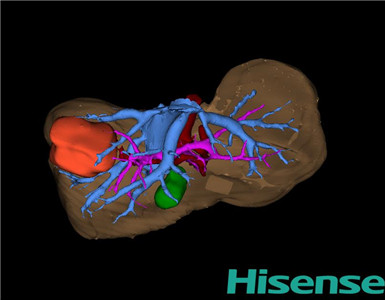

CT结果输入海信CAS系统后行3D重建:

术前三维重建及手术方案设计:

将0.625mm双源薄层CT资料的静脉期和动脉期Dicom格式文件导入海信CAS系统。

通过调节窗宽窗位调整CT序号,对肝实质,胆囊,下腔静脉,肿瘤,肝动脉、门静脉及肝静脉等进行三维重建;系统自动计算肿瘤体积和肝脏体积。模拟手术操作,自动计算切除肝体积、肿瘤体积、剩余功能性肝体积。肝脏体积为263ml,肿瘤体积为9.7ml,肿瘤体积为肝脏体积的3.9%,通过比对6-9月正常肝脏体积为257.75±51.05ml,通过术前模拟手术,精准判断切除后剩余肝脏体积能耐受,避免肝衰竭发生。

术前三维重建:

重建图片